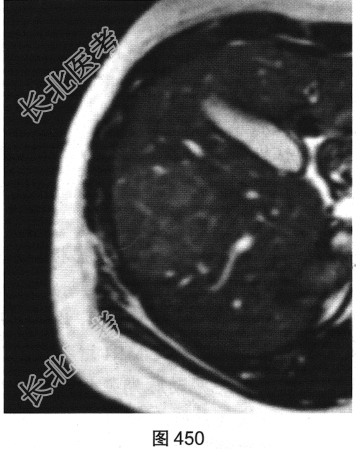

- 多项选择题3.[提示]随后患者接受上腹部MRI检查,如图449~图452所示。对患者MRI检查图像描述不正确的是( )

A、纤维瘢痕呈延迟强化

B、门静脉期病灶轻度强化

C、T1WI示病灶为稍低信号

D、动脉期病灶明显强化

E、T2WI示病灶为稍高信号

F、病灶内无纤维瘢痕